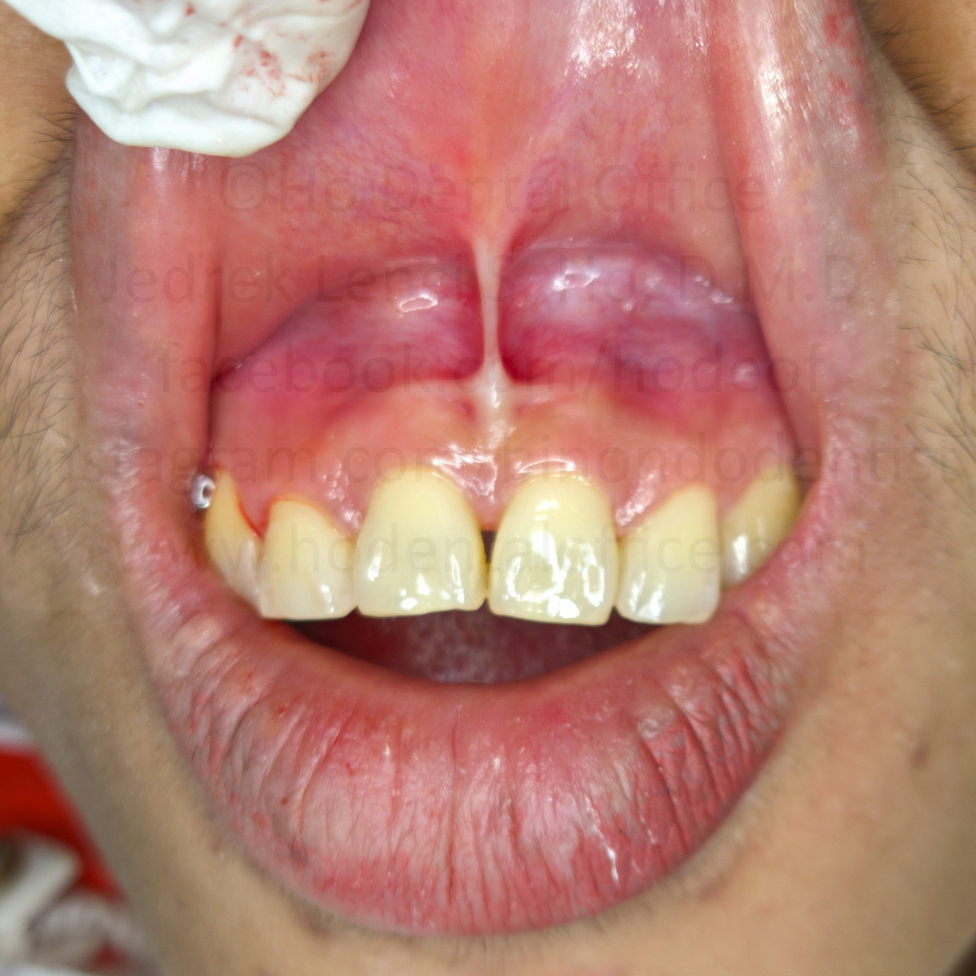

A few days later, patient underwent the procedure, under local anesthesia, using a scalpel. An electrosurgical unit would have been preferable, but I did not have that machine at that time. Surgical site was sutured afterwards using silk, and was removed a week later. The site healed without any issues.

Frenum reattachment was evident by June 2017, but not to the same extent as it was before surgery.